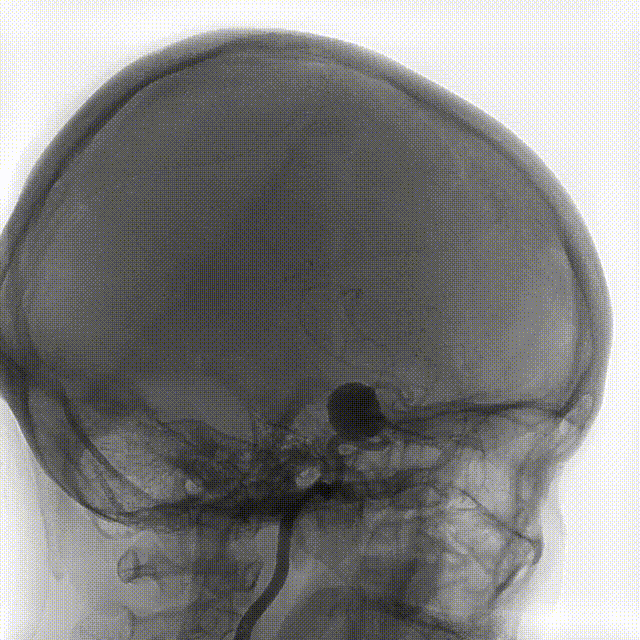

术中DSA造影:右侧颈内动脉正、侧位造影,显示右侧颈内动脉床突旁大型动脉瘤。

术中DSA造影:右侧颈内动脉3D造影提示:右侧颈内动脉床突旁大型动脉瘤,大小约为20.72×16.33mm,远端血管直径1.92mm,近端血管直径3.48mm。